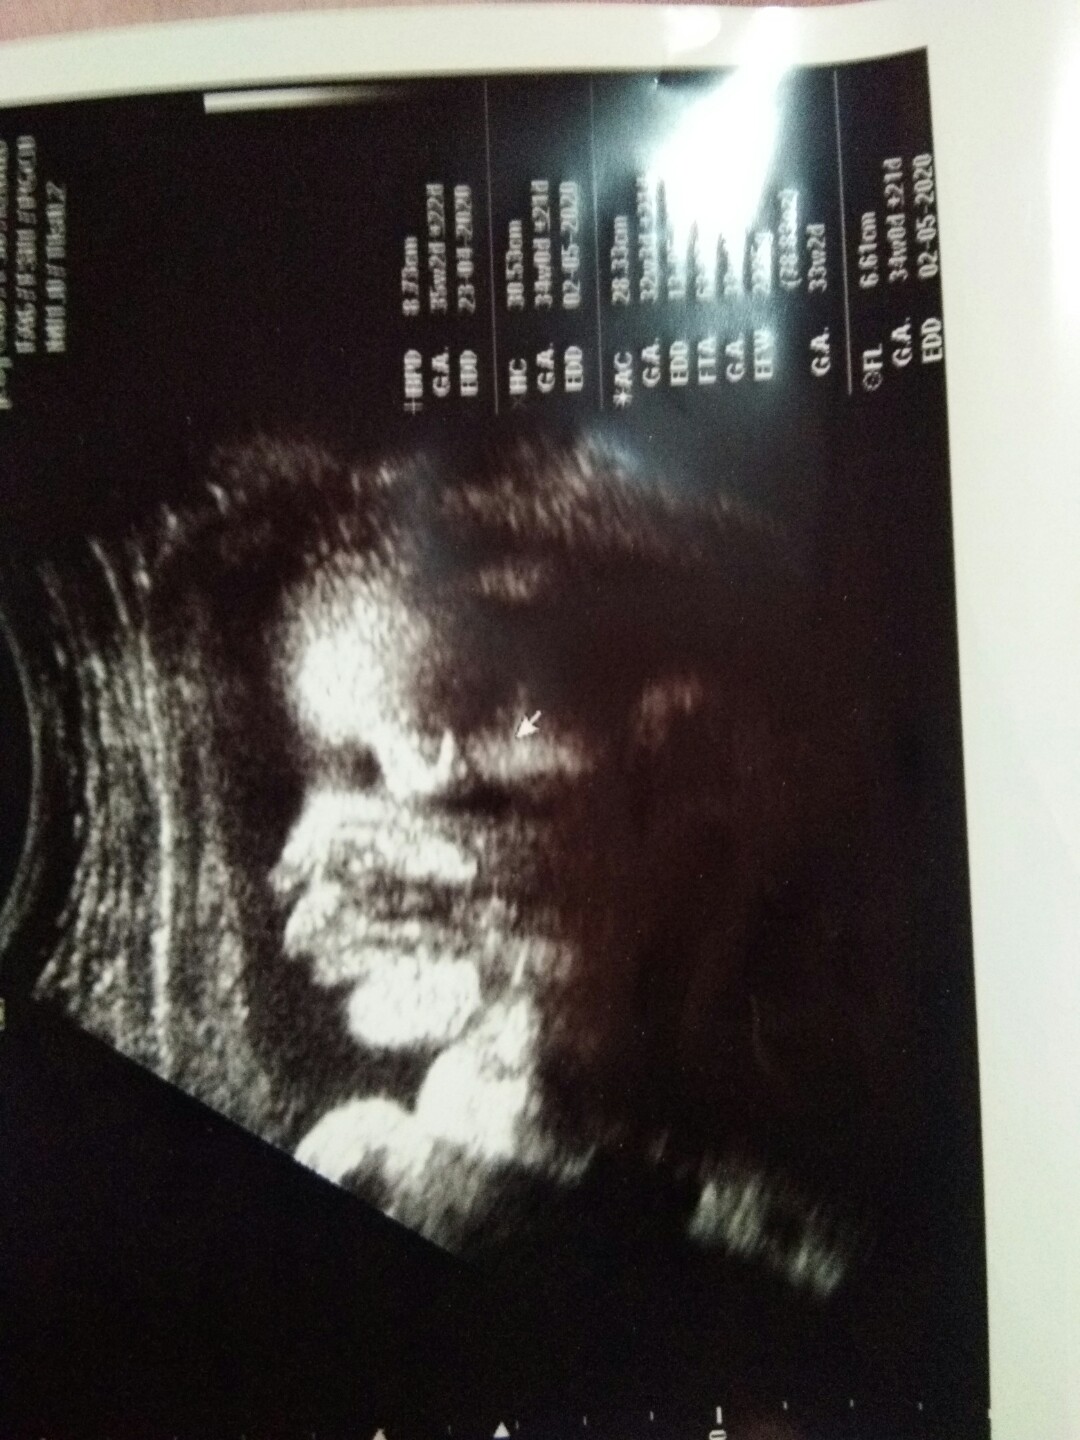

มีบ้านไหนซาวด์แล้วจมูกโด่งแบบนี้มั้ยคะ ออกมาจมูกน้องโด่งแบบนี้รึเปล่า? นี่คุณหมอบอกโด่งมาก?

เป็นแบบนี้ค่ะ